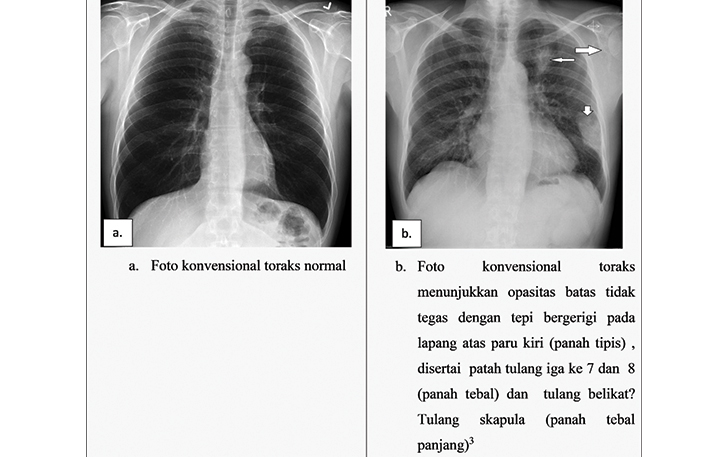

Berdasarkan guideline yang ditetapkan oleh Komite Penanggulangan Kanker Nasional Indonesia, pemeriksaan foto toraks untuk skrining kanker paru, menjadi pilihan yang tepat, agar kanker paru dapat terdiagnosis pada fase awal, pada penelitian cohort populasi besar, terdapat penurunan mortalitas sebesar 18 persen. Jika ditemukan lesi yang dicurigai sebagai keganasan, maka diperlukan pemeriksaan CT (Computed Tomography) scan toraks untuk penegakan diagnosis penyakit, staging/stadium dan evaluasi terapi.

Pada CT, gambaran yang sering ditemukan pada kanker paru meliputi massa soliter berlobulasi maupun tidak disertai tepi yang  bergerigi atau spikulasi. Penemuan ini juga dapat disertai dengan penyempitan atau sumbatan pada saluran napas bronkhial, menyebar ke pembuluh darah  arteri pulmonal, vena cava, serta efusi pleura maupun nodul pleura. (*)